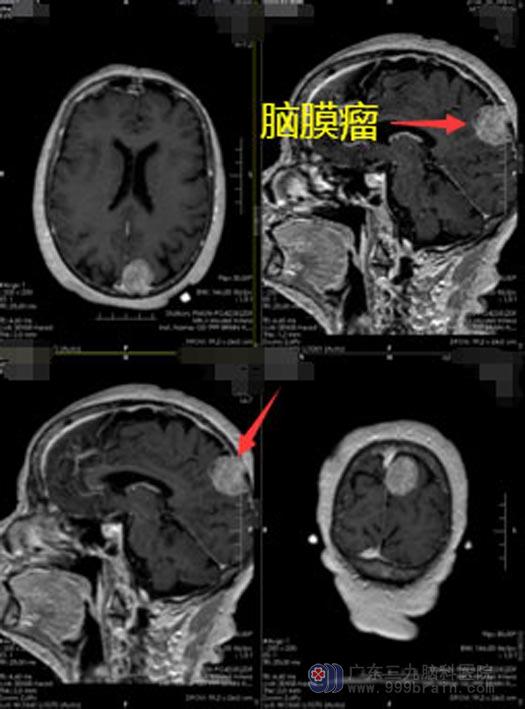

进一步完善相关的检查,明确张奶奶是左侧顶部占位性病变,考虑良性肿瘤。神经外五科鲁明团队很快就制定了手术方案,在全麻下行左侧顶部肿瘤切除术,肿瘤镜下全切,术中出血量很少。

▲手术前